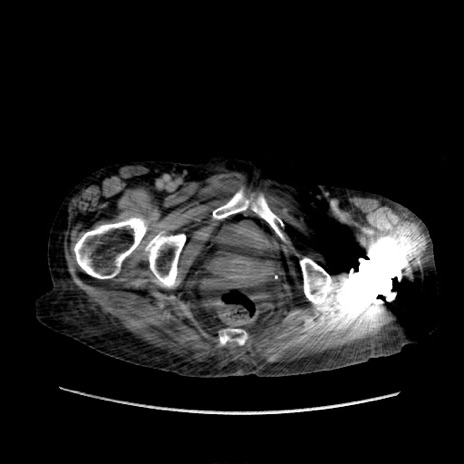

症例31(横断像)

【症例】80歳代 女性

【主訴】腹部膨満感

【現病歴】他院にて肝硬変にてフォロー中。1週間前から便秘、腹部膨満感、臍部腫瘤あり受診となる。

【既往歴】肝硬変

【身体所見】腹部膨隆あり、皮膚変化なし、疼痛なし。

【データ】WBC 4600、CRP 0.25